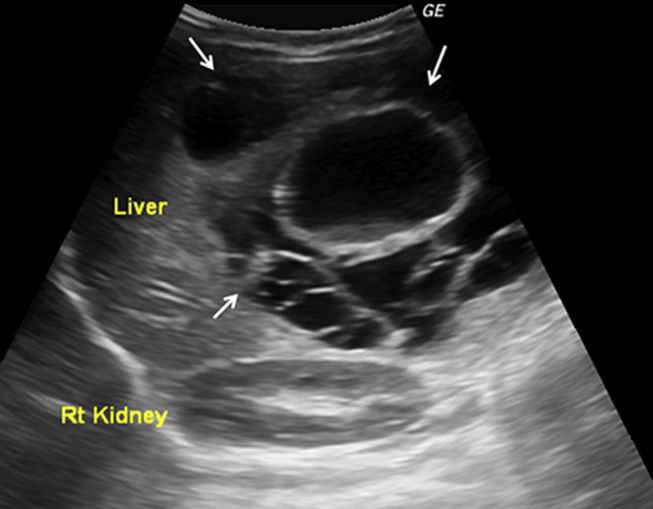

Fig. 1.

Ultrasonographic image showing a large multiloculated cystic hepatic mass (white arrows). Cysts of variable sizes and echogenic debris noted within the large central cyst.

A 10 month old male infant patient, an issue of non-consanguineous marriage and born normally at full-term, was brought to hospital with a painless right upper abdominal lump. This lump was noted over the last one month. There was no history of fever, vomiting, jaundice or haematuria. The baby's weight gain and achievement of milestones had been normal. On examination, the baby was active, playful and weighed 9.0 kg. He had a protuberant abdomen. There was hepatomegaly with a span of 13.0 cm. A firm, non-tender mass with a smooth surface was evident arising from the right lobe of the liver. There was no splenomegaly. The liver function tests and enzymes including serum alpha-fetoprotein (AFP) and gamma-glutamyl transpeptidase (GGT) were normal. All haematological and other biochemical tests were also normal. Test for echinococcal antigen was negative. Ultrasonography (USG) revealed a large well-circumscribed multicystic mass measuring 10.0 cm × 10.0 cm × 11.0 cm in the right lobe of the liver. The cysts measured 2.0 cm–5.0 cm in size. The cyst walls were 2.0 mm–4.5 mm thick with areas of irregularity; however there were no mural nodules or calcific foci. Debris was noted in the dependent part of the larger cysts (Fig. 1). A few small solid areas that were heterogeneously hypoechoic were noted between the cysts. On colour-Doppler flow imaging, there was no evidence of increased vascularity. A subsequent non-contrast and contrast-enhanced computerized tomography (CT) of the abdomen revealed a well-defined multicystic mass measuring 10.0 cm × 11.0 cm × 12.0 cm involving almost the entire right hepatic lobe. The central and peripheral cysts had an attenuation of 4 Hounsfield Units (HU) and 17 HU, respectively. The cyst walls revealed contrast-enhancement. A few small solid areas of enhancement were also noted between the cysts (Fig. 2). The rest of the abdomen was normal. Based on the clinical presentation and imaging findings, a diagnosis of hepatic MH was made. The infant underwent surgical intervention in the form of marsupialization with uneventful post-surgical recovery. Biopsy from the lesion at surgery confirmed the imaging diagnosis.